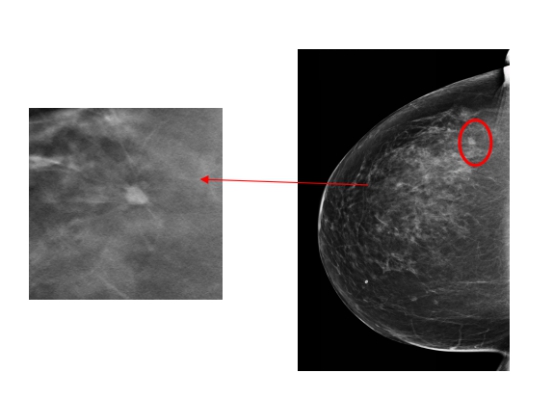

哈医大一院放射科主任陈颖教授介绍,由于李女士比较年轻,属于致密型乳腺,常规的乳腺钼靶摄片未发现明显的肿块,仅显示双乳增生及良性钙化。数字化乳腺断层摄影断层图像显示左乳外上象限长了一个5mm的结节,经放射线科钼靶室医生会诊发现,该结节有很大可能性是恶性的乳腺癌,因此建议李女士做活检或者入院手术治疗。术中冰冻切片发现该结节是乳腺原位癌,因此医生为她制定了保乳手术的治疗方案,目前正在康复中。术后,李女士特意打电话感谢放射线科的医生们帮助她及早地发现了这个病灶。

2020年末哈医大一院放射线科引进(HOLOGIC)数字化断层乳腺机,与传统的数字化钼靶乳腺机相比,能够最大限度地减少乳腺组织重叠,尤其是对年轻东方女性的致密型乳腺能够明显提高病灶检出率,大大降低了假阳性率及假阴性率。